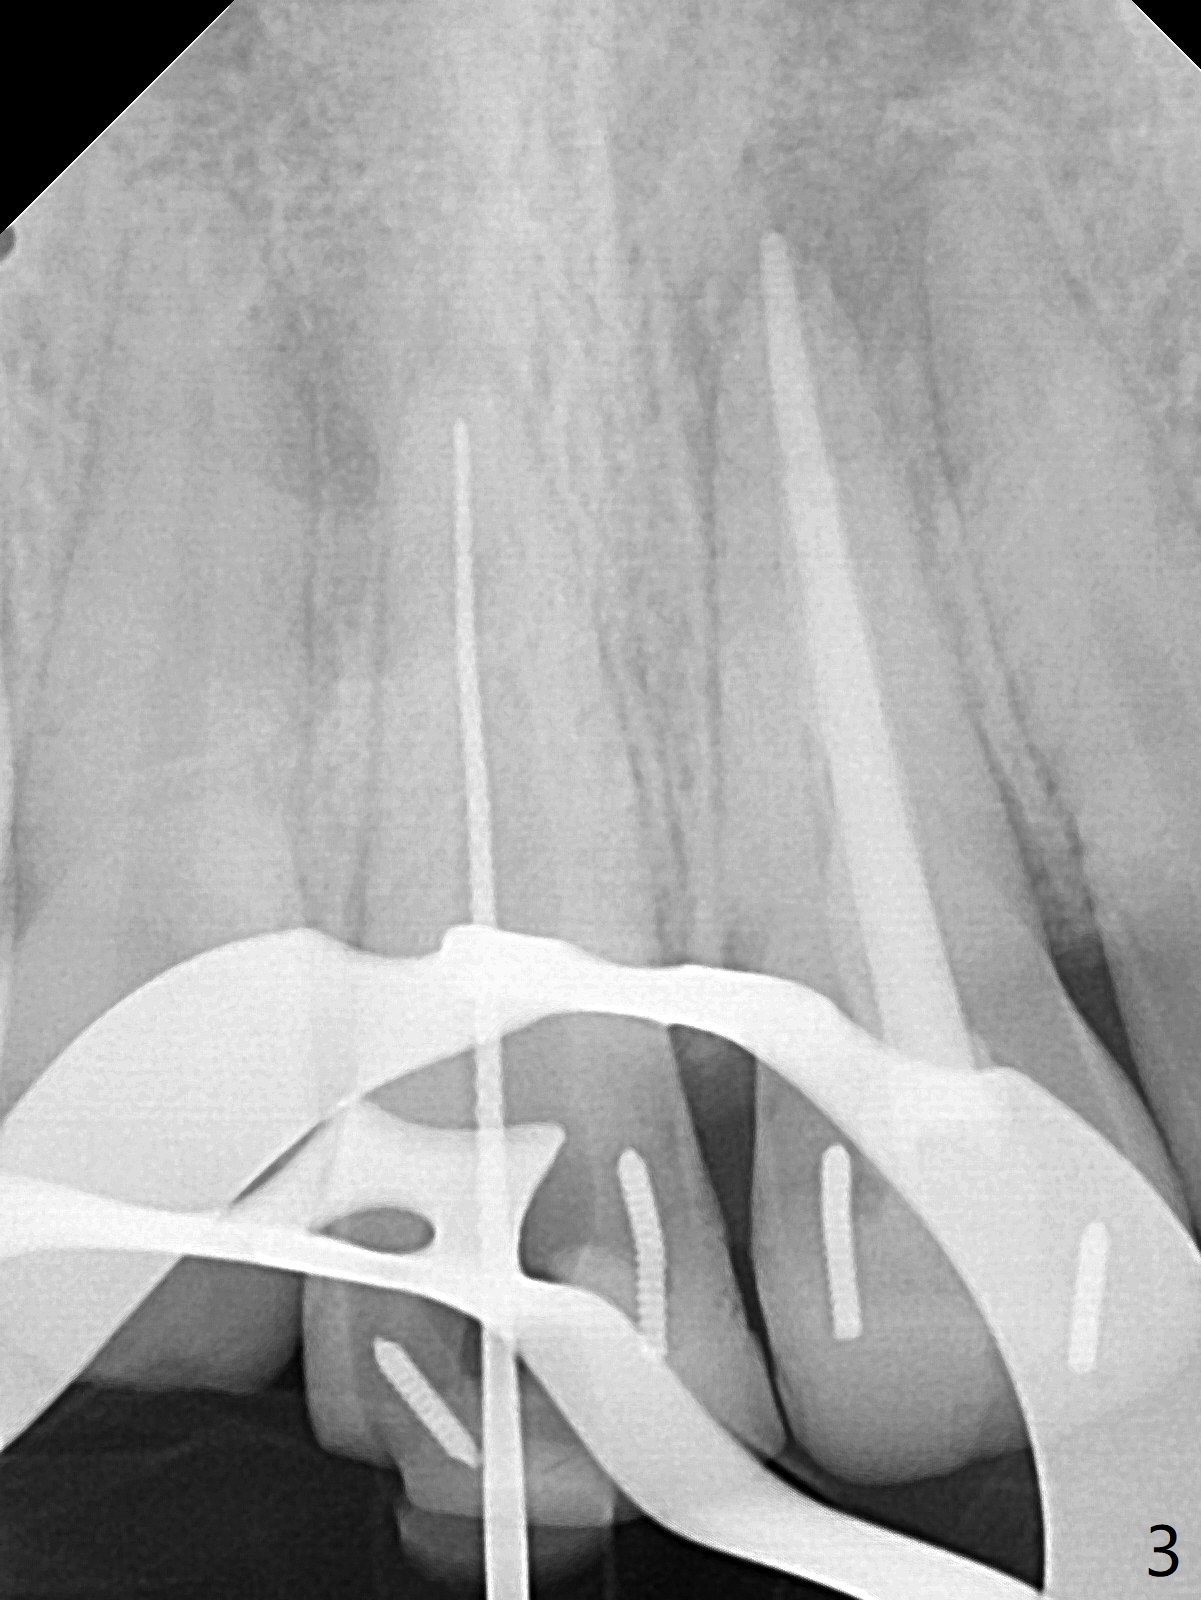

15岁男去年急诊来诊所左上1疼痛(图一:9号牙),两个中切牙8-9岁外伤,侧切牙活性测定:活髓,建议8,9 apexification。一年后(这个月)他又回来要求9号牙树脂修复(图二:*),他在马来西亚看望爸爸时,突然牙痛在那里做根管治疗。现在两个中切牙颊侧根尖都有触痛。树脂修补后,他回来做8号牙牙髓治疗,想象根管宽大,但是根尖2-3毫米根管弯曲,必须事先弯曲10号扩大针才能进入,最后扩大针是rotary file, 40/.04, 21.5毫米(图三),好像工作长度不够,仅仅增加半个毫米,使用15号扩大针,病人觉得疼痛(没用局麻药),不再扩大,保持原来根尖狭窄(可以吗?)。反复冲洗后放置氢氧化钙糊剂(图四),根管仿佛挺粗的,根尖根管还需要扩大吗?根尖片清晰度不好,看不出根尖闭锁与否,需要拍摄CT吗?需要使用MTA促进根尖关闭吗?